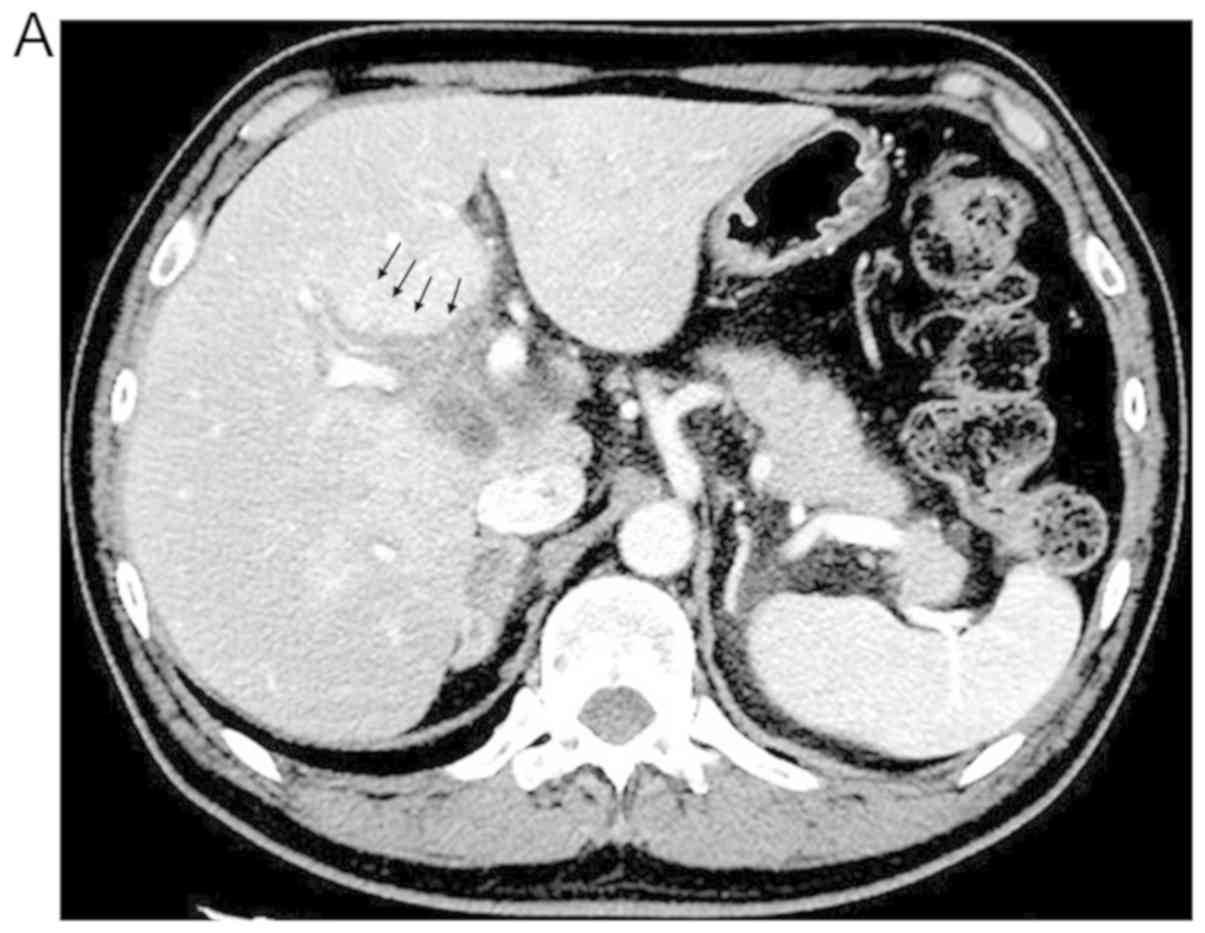

Nivolumab‑induced cholangitis in patients with non‑small cell lung cancer: Case series and a review of literature

Immune checkpoint inhibitors (ICIs), including nivolumab, have exhibited substantial benefits in the treatment of several types of cancers. However, treatment with ICIs is often accompanied by immune‑related adverse events (irAEs), and a clear understanding of the precise indications and management of irAEs is important for harnessing the full potential of these agents. While skin‑ or gastrointestinal‑associated irAEs have been relatively well studied, there are few reports regarding nivolumab‑induced cholangitis. We retrospectively reviewed data from patients with advanced or recurrent non‑small cell lung cancer who were treated with nivolumab between December 2015 and December 2018 at Tottori University in Japan. Among the 59 patients, we identified four patients who experienced nivolumab‑induced cholangitis. Of these four patients, stable disease (SD) was observed in two patients (50%), while partial response (PR) was achieved in two patients (50%) under nivolumab treatment. Patients were treated with corticosteroid alone (n=2) or in combination with mycophenolate mofetil (MMF) (n=2); these treatments resulted in improvements in nivolumab‑induced cholangitis in three patients. In conclusion, the present retrospective study identified four cases of nivolumab‑induced cholangitis. The combination of corticosteroid and MMF was effective in two cases with grade 4 nivolumab‑induced cholangitis. Further reports are needed to establish the optimal management of patients with this irAE.

Figure 1

Figure 2